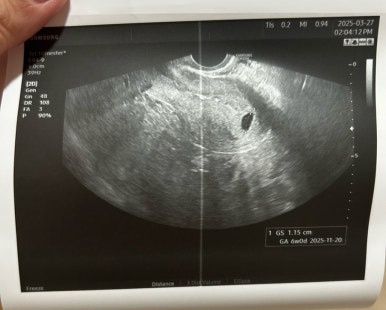

(3/20 아기집 , 3/27 난황)

아기집은 1.15cm로 커졌고

그 안에 0.46cm의 난황이 생겼다 !!!

이 시기에만 볼 수 있다는 다이아몬드💍

화질이 엄청 선명하진 않지만

난황도 잘 커졌고, 그 위에 예쁘게 자리잡은 사탕이

사탕이는 그새 커서 0.37cm가 되었다👼🏻

(주기는 좀 밀려 5주로)